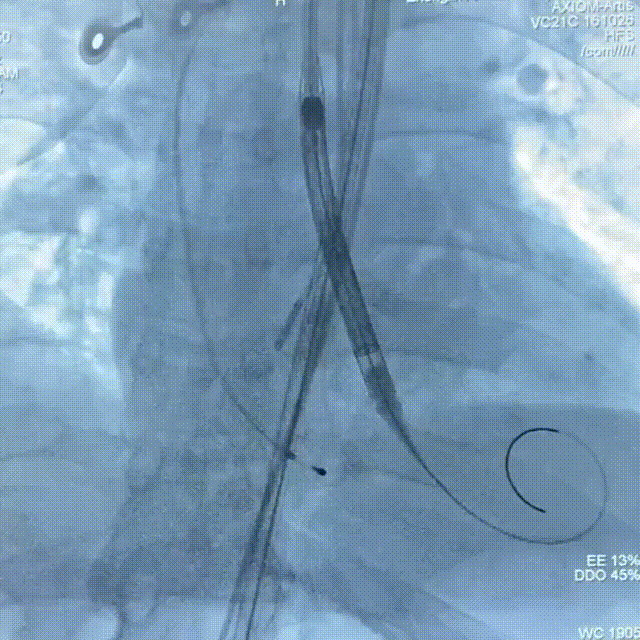

术中操作

18mm球囊预扩

TAV24瓣膜精准定位

缓慢释放至1/3

瓣膜脱钩释放

22mm球囊后扩

术后造影